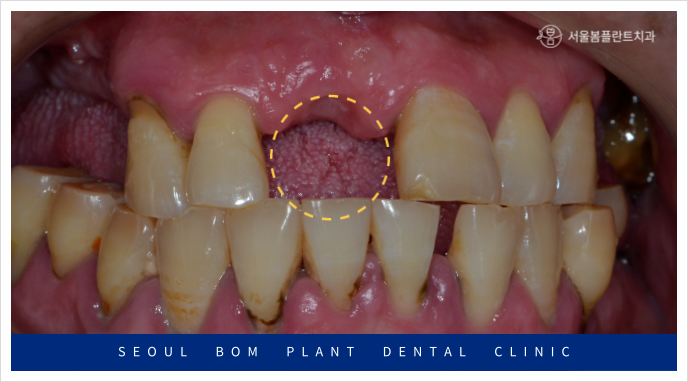

오늘은 위턱 앞니의 임플란트 탈락으로

송파구치과 서울봄플란트치과를

내원해 주신 사례를

소개해 드리겠습니다.

환자분께서는 50대 초반의

남성분으로 타 치과에서 했던

오른쪽 위턱 첫 번째 앞니(#11)의

임플란트가 빠져 상담을 위해

내원해 주셨는데요.

앞니는 원래도 잇몸뼈가 얇은 데다가

환자분께서는 임플란트 주위염으로 인해

잔존 잇몸뼈가 약해져

기존 임플란트가 탈락한 상황이었는데요.